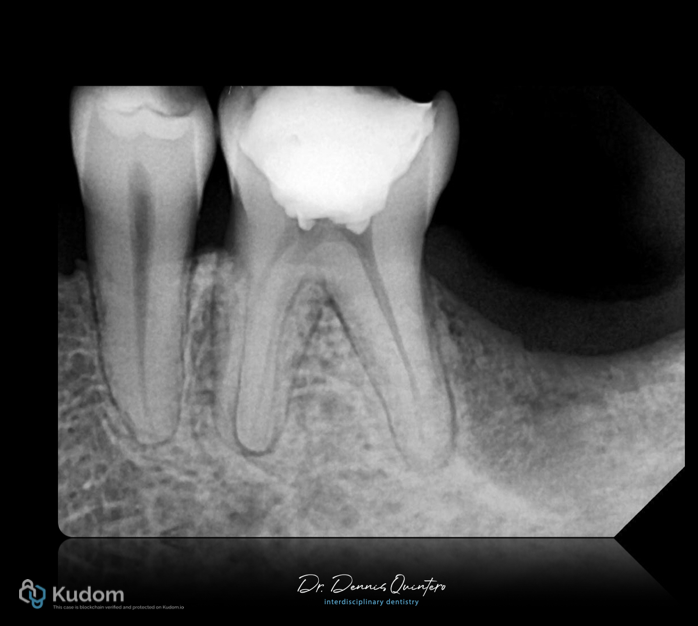

Fig. 1

. Tooth 3.6

. Initial X-ray with deep provisional material close to the pulp.